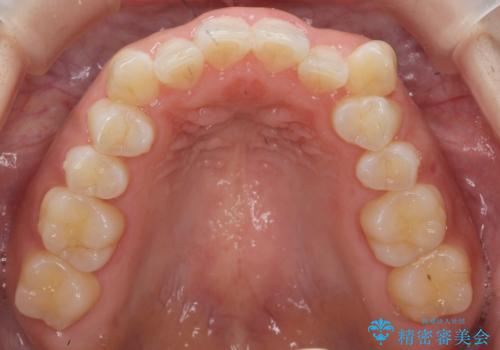

八重歯を非抜歯で マウスピースで治療 奥歯を後ろに下げてすき間を確保

- 八重歯を主訴に来院。

奥歯を後ろに下げてすき間を確保し、八重歯を引っ込めて並べる治療を行いました。

奥歯を後ろに下げるために、矯正用のミニスクリューを使用しています。